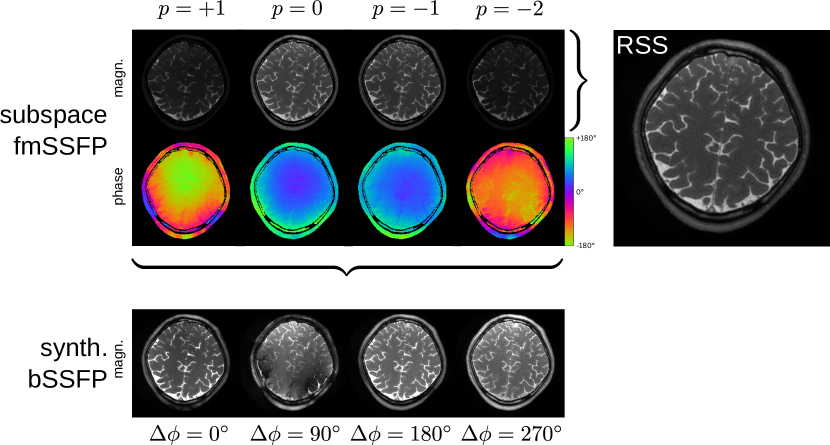

Refer to caption

Figure 8: Reconstructed subspace coefficients maps (top) along with its root-sum-squares composite image for a individual slice within the acquired 3D volume. Synthesized bSSFP images are computed from these coefficient maps for different virtual frequency offsets (bottom).

Conventional balanced steady-state free precession (bSSFP) sequences exhibit a high signal-to-noise ratio (SNR) but suffer from possible signal voids in regions with certain off-resonance distributions. These voids or banding artifacts can be removed when multiple images are acquired with different transmitter phase cycles. Foxall and coworkers demonstrated that bSSFP sequences are tolerant to small but continuous changes in transmitter frequency [53]. In [49] we exploited this method to develop a time-efficient alternative to phase-cycled bSSFP that waives intermediate preparation phases in phase-cycled bSSFP to establish different steady-states. Image reconstruction is performed in the low-frequency Fourier subspace and yields signal intensity and contrast comparable to on-resonant bSSFP.

To this end, a frequency-modulated SSFP (fmSSFP) pulse sequence [53] was combined with 3D stack-of-stars data acquisition such that a single full sweep through the spectral response profile was obtained. Aligned partitions allowed to decouple the reconstruction problem into individual slices by a 1D inverse Fourier transform. After coil sensitivity estimation [54], image reconstruction was performed by solving a linear subspace-constrained reconstruction problem using a local low rank regularization. As a subspace basis, the four lowest order Fourier modes were chosen. Figure 8 shows the reconstructed complex-valued coefficient maps from which a composite image can be computed in a root-sum-squares manner (top). Additionally, synthesized bSSFP images are computed for four virtual frequency offsets (bottom) in which the distribution of signal voids is given by the phase distribution of the subspace coefficients. These synthesized bSSFP images correspond to conventional bSSFP images acquired with four different phase cycles.